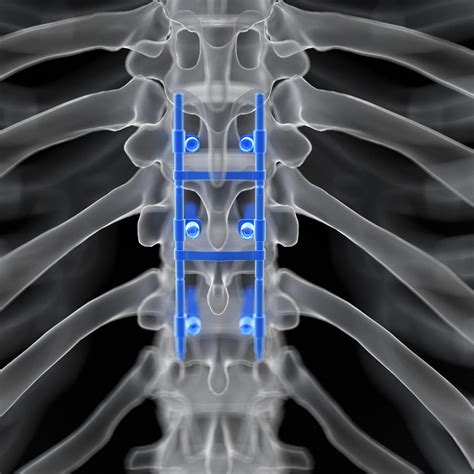

• Stabilization: Additional hardware, such as screws, rods, or plates, may be used to stabilize the spine and promote fusion.